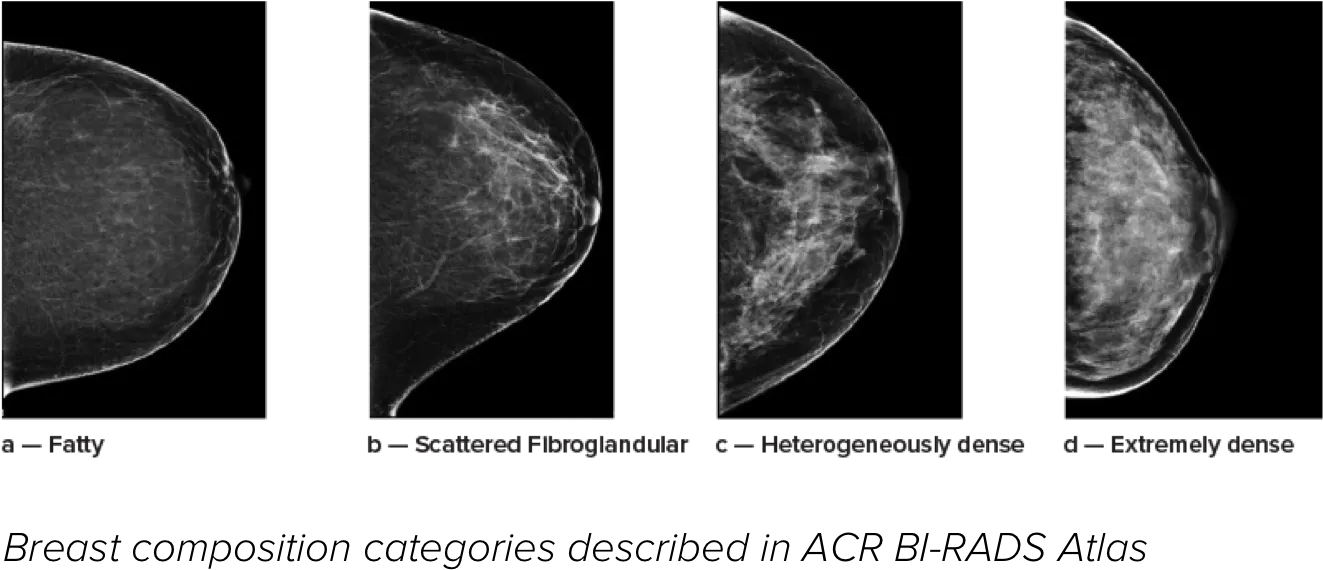

Higher breast density is known to increase a woman’s risk for breast cancer.1 The need for accurate, unbiased analysis is therefore critical. Powered by machine learning, Quantra technology software analyses both 2D™ and tomosynthesis images for distribution and texture of parenchymal tissue. It categorises breasts in four breast composition categories consistent with guidance from the American College of Radiology (ACR) BI-RADS Atlas 5th Edition.2

*Scores are based on ACR BI-RADS categories, in line with the revised guidance by the American College of Radiation (ACR) BI-RADS Atlas 5th Edition. This accounts for pattern and texture, compared with volume, when determining density.

8. Breast composition categories as described in ACR BI-RADS Atlas.